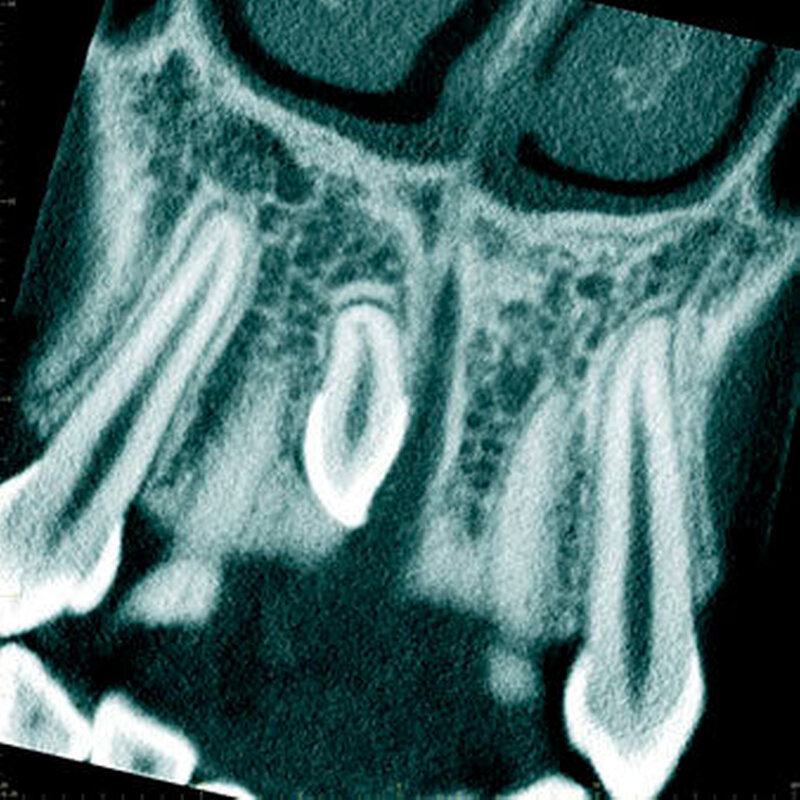

In einer aktuellen Arbeit berichteten Mossaz und Mitarbeiter (2014) über eine relativ hohe Prävalenz (22,8 Prozent) der Wurzel- resorptionen an benachbarten Zähnen, wobei besonders häufig überzählige Prämolaren zu Resorptionen führen (Abbildung 18). Für die Beurteilung der Wurzelresorptionen wurden digitale Volumentomografie (DVT) der Patienten herangezogen. In einer Studie aus China, welche ebenfalls DVT-Bilder beurteilte, wurde über eine deutlich geringere Häufigkeit von Wurzelresorptionen (1,6 Prozent) berichtet [Liu et al., 2007]. Im Gegensatz zu den Daten aus der Schweiz war Diagnose und Bewertung von Wurzelresorptionen kein primäres Ziel dieser Studie und es wurde auch keine Information über das Ausmaß der Resorptionen gegeben.

Daher könnte diese Studie leichte oder mäßige Wurzelresorptionen nicht eingeschlossen haben, was zumindest einen Teil des doch deutlichen Unterschieds in den Prozentsätzen erklären würde. Studien, welche Panoramaschichtaufnahmen zur Diagnose von Wurzelresorptionen heranziehen, berichten über Resorptionsraten zwischen 4,7 Prozent [Gündüz et al., 2008] und 7,6 Prozent [Hyun et al., 2009]. Tyrologou und Mitarbeiter (2005) berichteten sogar, dass keine Resorption im untersuchten Patientengut vorhanden waren. Allerdings wurden in dieser Studien nur Mesiodentes beurteilt, wo Wurzelresorption benachbarter Zähne eher selten vorkommen [Mossaz et al., 2014]. Generell lässt sich festhalten, dass zweidimensionale Röntgenaufnahmen für die Diagnose von Wurzelresorptionen eher ungenau sind und diese so in bis zu 50 Prozent der Fälle übersehen werden [Ericson Kurol, 1987, Heimisdottir et al., 2005; Botticelli et al., 2011; Alqerban et al., 2011a].